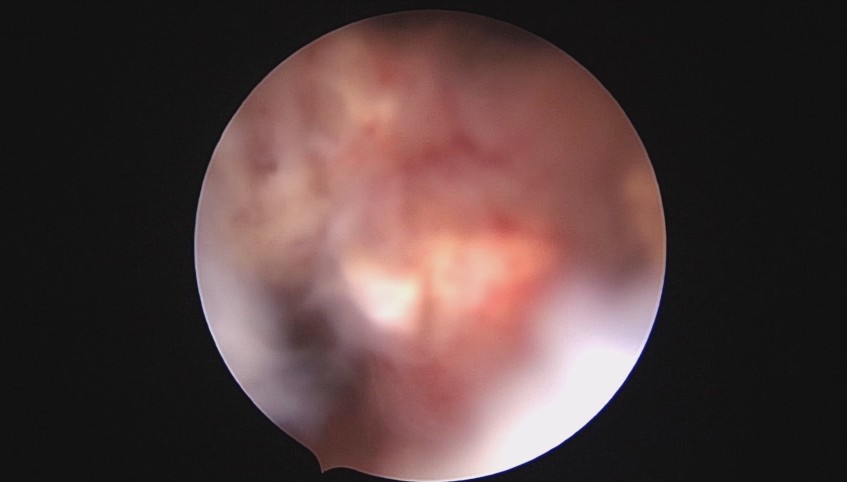

患者28岁,G7P3,顺产3次,完全纵膈子宫,单宫颈。2015年、2018年顺产,2019年左侧宫腔计划外妊娠行宫腔镜取胚及左侧宫腔放置γ环(推测既往妊娠左侧宫腔妊娠可能性大)。2023年4月带环受孕(应该为右侧宫腔妊娠),2023年12月足月阴道分娩,分娩时试图取出左侧宫腔内节育器,因操作困难,取环失败。2024年2月顺产后67天,要求取出宫内节育器,左手臂放置皮埋避孕棒。B超提示环距宫底1.1cm,环两翼分别距子宫前壁浆膜面0.4cm,距子宫后壁浆膜面0.3cm。宫腔镜术中膨宫困难,见宫颈管及宫腔少许淡黄色脓液流出,γ环逆时针旋转约80度,两臂指向左侧宫腔前后壁(2019年放置环时亦如此,因单侧宫腔前后径大于横径所致)。异物钳取出节育环,左右侧宫腔均见散在黄色机化组织,未取病检。